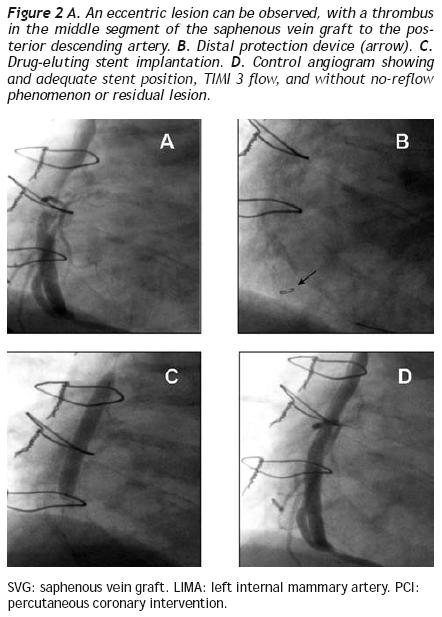

All PCIs were performed according to standard techniques. All patients received 300 to 600 mg of clopidogrel or ticlopidine (250 mg) and aspirin (100 mg) before the procedure; aspirin was continued indefinitely and clopidogrel (75 mg) for at least 3 months after the implantation of bare–metal stents and during 9 months after drug–eluting stent (DES) placement. Non–fractionated heparin was administered during the procedure to obtain an activated clotting time > 250 s. The operator decided the type of stent, the use of a distal protection device, the direct stenting technique, as well as the administration of glycoprotein IIb/IIIa inhibitors (Figure 2).